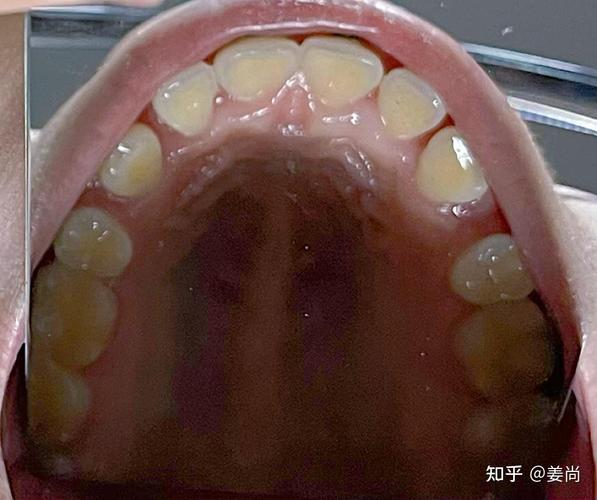

错位牙在口腔正畸中表现为牙齿偏离牙弓正常位置或排列异常,根据形态特征可分为以下几类,具体如下表:

| 类型 | 特征描述 | 临床表现 |

|---|---|---|

| 扭转牙 | 牙齿围绕长轴发生旋转,如上颌侧切牙“拧”着生长,或前磨牙旋转90°以上。 | 牙齿唇舌/颊舌侧厚度不均,刷牙时清洁死角多,易堆积牙菌斑;相邻牙齿间出现“三角间隙”,食物嵌塞频繁。 |

| 唇/舌向错位牙 | 牙齿偏离牙弓正常弧线,向唇侧(俗称“龅牙”)或舌侧(俗称“地包天”的部分表现)过度突出。 | 唇侧错位牙可能影响美观,微笑时露齿过多;舌侧错位牙易与对颌牙形成咬合干扰,导致咀嚼疼痛。 |

| 高位/低位错位牙 | 牙齿萌出或移动后,高于或低于牙平面,如“深覆合”时上前牙过低,或“开合”时后牙低位。 | 高位牙可能咬伤对颌牙龈,导致溃疡;低位牙与对颌牙无接触,咀嚼效率低,长期可能引发颞下颌关节紊乱。 |

| 近远中错位牙 | 牙齿在牙弓中前后位置异常,如尖牙(“虎牙”)向近中倾斜,占据侧切牙位置;或磨牙近中移动过多。 | 牙齿间邻接关系破坏,食物嵌塞;咬合时受力点偏移,易导致牙周组织创伤或牙齿松动。 |